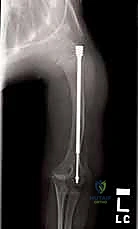

الخطوة الرابعة: إدخال المسمار التلسكوبي

بعد تقويم العظم وجعله مستقيماً كحبات المسبحة على خيط، يتم إدخال السلك الدليلي (Guide Wire). ثم يتم إدخال الجزء الخارجي (الأنثوي) من المسمار التلسكوبي وتثبيته في الجزء العلوي من العظم (Epiphysis).

بعد ذلك، يتم إدخال الجزء الداخلي (الذكري) من المسمار عبر الجزء السفلي من العظم وتثبيته في المشاشة السفلية. هذا التصميم العبقري يضمن حماية العظم بالكامل من الداخل.

كان عمار يعاني من النوع الثالث من تخلّق العظم الناقص، مع تقوس شديد في عظمي الفخذين (بشكل حرف O) منعه من المشي تماماً، وجعله حبيس الكرسي المتحرك، مع تاريخ من 8 كسور سابقة. تم إجراء عملية بضع العظم المتعدد عبر الجلد وتركيب مسامير فاسييه-دوفال التلسكوبية في كلتا الساقين في جلسة جراحية واحدة بواسطة الدكتور هطيف. اليوم، وبعد 6 أشهر من الجراحة، يمشي عمار مستقلاً لأول مرة في حياته، ولم يتعرض لأي كسر جديد.

عانت رؤى من كسور متكررة في عظم القصبة (الساق) بمجرد محاولتها الجري. أظهرت الأشعة هشاشة شديدة وتقوساً أمامياً. بعد استشارة الأستاذ الدكتور محمد هطيف، تقرر إجراء التدخل الجراحي المحدود. تم تصحيح التقوس بنجاح باهر، وبفضل المسمار التلسكوبي الذي ينمو معها، عادت رؤى للعب مع أقرانها بثقة وأمان.